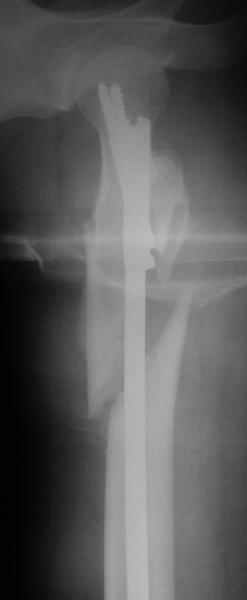

Другое наблюдение:Мужчина, 1957 г.р. Травма в результате ДТП 12.09.04г.

Диагноз: Закрытый оскольчатый подвертельный перелом правой бедренной кости со смещением отломков, оскольчатый перелом большого вертела, отрывной перелом малого вертела.Сопутствующие заболевания: Язвенная болезнь желудка, ремиссия.

Наверно, можно и так сказать, но можно и тоже самое - 4-фрагментный вертельный перелом. Выбор тот же, но с учетом молодого возраста реконструкционный гвоздь тут более применим. Вот уже наш пример.

Перелом подвертельный. Лечение оперативное, срочное,

PFN с длинной ножкой чтобы избежать стрессовые изменения в будущем. Обычно у молодых людей требуется проводить рассверливание канала как при гвоздевании.

В данной ситуации я бы провел остеосинтез при использовании длинного Gamma Nail